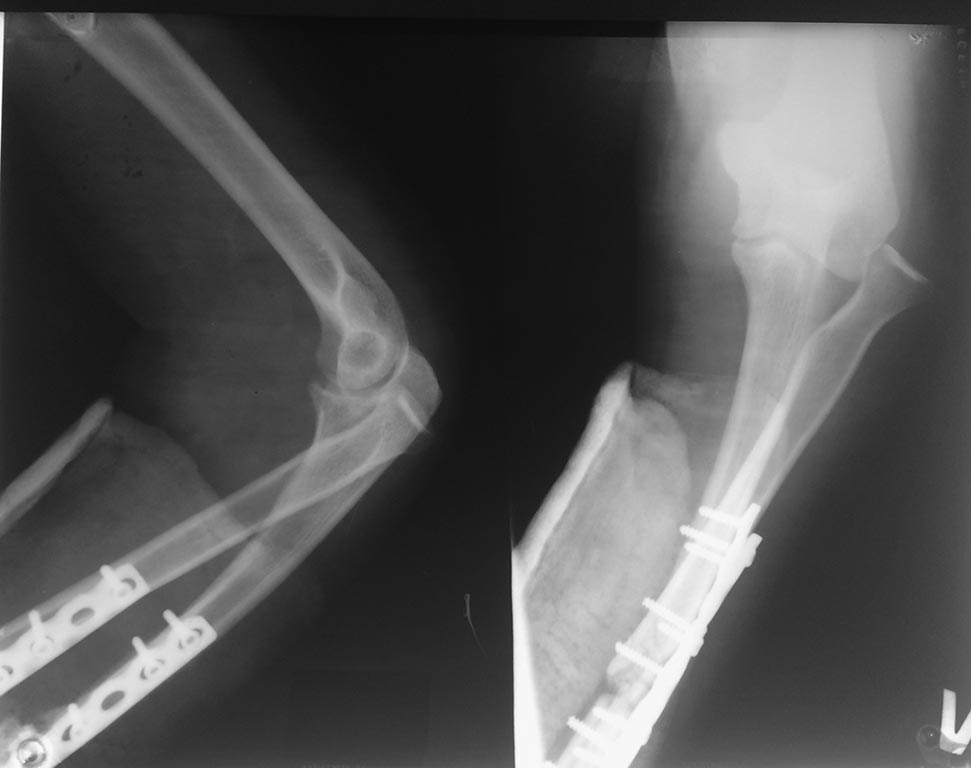

Застарелый вывих головки луча

Молодая пациентка. Травма несколько месяцев назад. Рука попала в тестомешалку. Открытый questilio 3. Перелом костей предплечь, открытый вывих в лучезапястном суставе. Дежурной бригадой сделано пхо, синтез костей предплечья. Все зажило, хотя не совмем гладко. А на контроле - вывих головки луча. Соотношение в дистальном лучелоктевом суставе правильное. Вопросы по объему операции:

Жалко нет снимков лучезаястного сустава, да и сам перелом захвачен краем? Нет ощущения что лучевая кость синтезирована с диастазом? Если так, то репозиция и ресинтез + возможно релиз в области головки луча Рашит проблему, при Необходимости т/а фиксация головки с головчатый сочленением спицами недельки на 3

Снимки не очень информативные. Но и по ним видно, что имеется диастаз между отломками лучевой кости и отсутствуют признаки консолидации. Так что если думать о реостеосинтезе, то лучевой, а не локтевой кости. С одновременным ее укорочением.

У нас тут псевдартроз костей предплечья, я бы начал с реостеосинтеза.

А с чем его сочетать? Это нам покажут снимки предплечья с пронацией и л/зап. сустава в двух проекциях, и тогда будем вправе исправить ось или укоротить лучевую, или эндопротезировать головку.